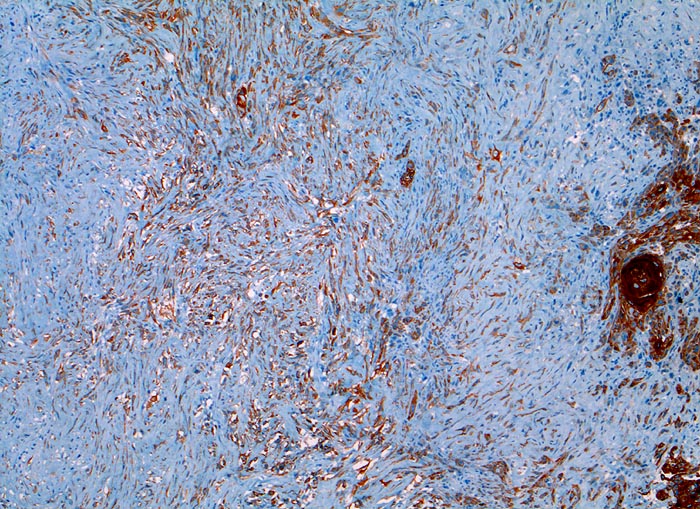

PathoPic – image database / PathoPic ID 3301 - sarkomatoides Plattenepithelkarzinom

sarkomatoides Plattenepithelkarzinom

Larynx

Der Panzytokeratinmarker Lu-5 färbt sowohl die plattenepithelial differenzierten verhornenden Tumor-Zellstränge rechts im Bild als auch ein Teil der sarkomatoiden entdifferenzierten Tumorkomponente an.

Tumor subglottisch rechts. Immunhistochemische Resultate: CK22, Lu-5, Vimentin positiv

Histologie

Immunhistochemie

Lu5 Panzytokeratin